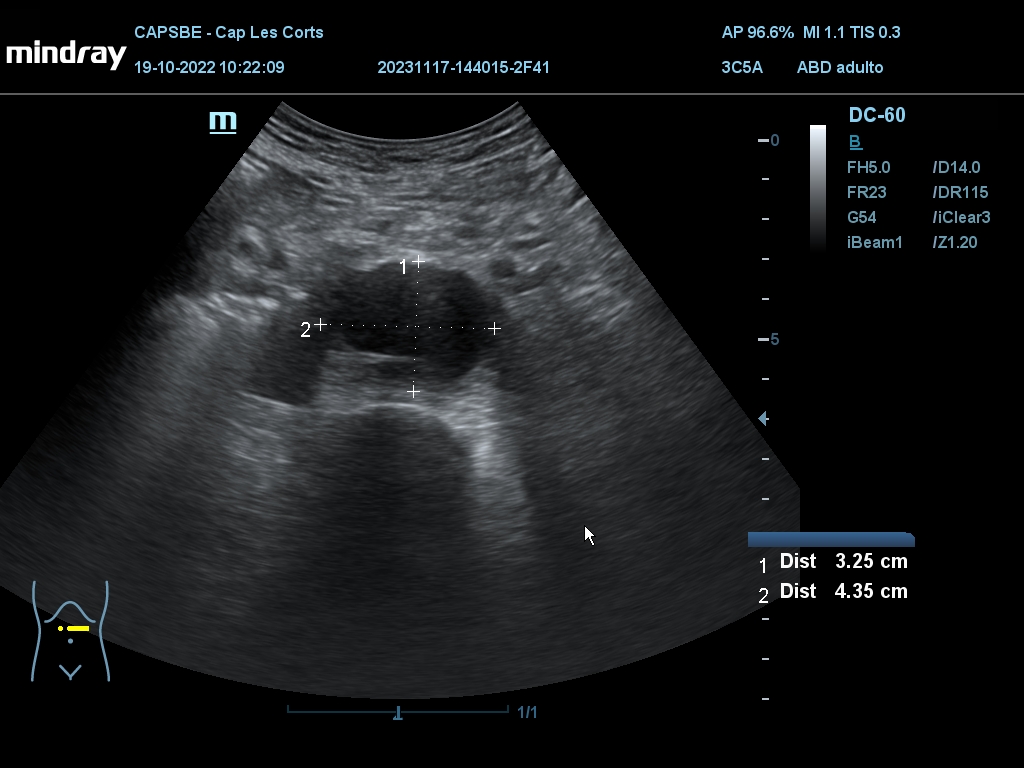

Hallazgos ecográficos

Derrame pericárdico. Vesícula biliar con grosor parietal de 1,6 cm, heterogénea, no se moviliza con cambios posturales. Quistes renales derechos, mayor de 7 cm. Aorta ateromatosa y aneurismática de 36 x 42 mm. Sin líquido intraabdominal.

(Se adjuntan imágenes del derrame, engrosamiento biliar, riñón derecho y aneurisma de aorta).